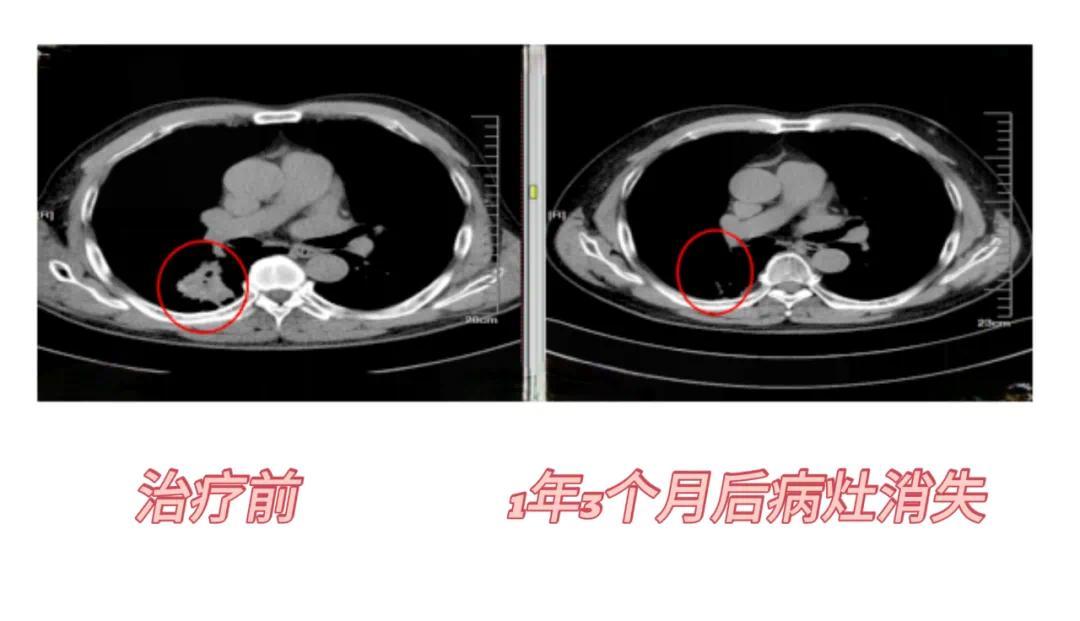

射波刀肺部病例:患者男性,58岁,胸部CT:右肺下叶背段见团块状高密度灶,边缘可见分叶及毛刺,大小约3.6*4.0cm;病理示:低分化腺恶性肿瘤。患者肺功能差不适合手术,选择射波刀治疗,1个月后复查病灶缩小,6个月后病灶进一步缩小,1年零3个月后病灶消失。